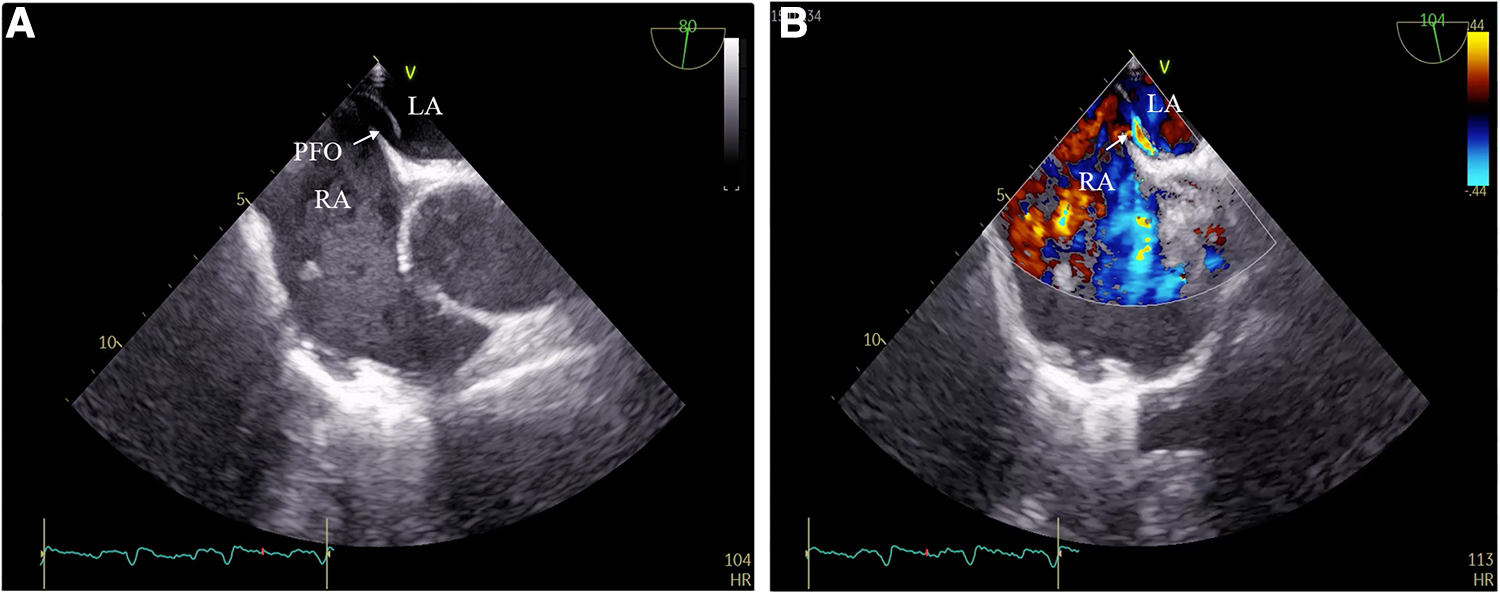

Figure 3

(A) PFO detected by transesophageal echocardiography; (B) right-to-left intracardiac shunt through PFO.

A 59-year-old woman was admitted due to pacemaker pocket infection. A dual-chamber pacemaker was implanted 14 years ago due to III degree atrioventricular block. No history of infiltrative cardiomyopathy, myocarditis, or coronary artery disease. There was also no history of cardiac surgery or connective tissue disease. The pacemaker pocket infection lasted for two months and was unresponsive to antibiotic therapy. There were no vegetations on the leads. Additionally, the blood cultures were negative. Indications for lead extraction were confirmed, and the patient informed consent was obtained. The atrial and ventricular leads were removed through the right femoral vein using a needle's eye snare (Figure 1). Hypoxemia (FiO2 61%/PaO2 64.3 mmHg) was observed immediately after the removal of the lead. Pericardial effusion was ruled out by x-ray fluoroscopy, and the pulmonary arteriogram did not show any filling defects in the main pulmonary arteries. The computed tomography pulmonary angiogram (CTPA) did not show any signs of pulmonary embolism, and the chest CT did not reveal any significant lesions. As peripheral pulmonary embolism could not be ruled out completely, anticoagulation therapy was initiated. Neither oxygen therapy with a mask (oxygen flow rate of 7.7 L/min) nor noninvasive mechanical ventilation (BiPAP: IPAP = 11 cmH2O, EPAP = 5 cmH2O, FiO2 = 100%) was effective in relieving hypoxemia. Pulse oxygen saturation (SpO2) was measured in both supine and upright positions. The results showed 89% in the supine position and 77% in the upright position (Figure 2). Therefore, we considered the diagnosis of Platypnea-Orthodeoxia. A PFO with intracardiac shunt was suspected. Transesophageal echocardiography revealed a PFO (see Supplementary material: Video 1 and 2), and right heart contrast echocardiography showed the presence of a right-to-left intracardiac shunt, without any signs of pulmonary hypertension or elevated pressure in the right heart (Figure 3). As the patient was pacemaker-dependent, a dual-chamber permanent pacemaker was re-implanted. After re-implantation, the patient's SPO2 levels were monitored at 82%–89% without oxygen inhalation. Although the patient was hypoxemic, her hemodynamic and metabolic parameters were normal. After 10 months of follow-up, the patient's hypoxemia persisted, with SPO2 levels at 88% (PaO2 52.3 mmHg) without oxygen inhalation (Figure 2). The patient also experienced with a decrease in exercise tolerance compared to her preoperative state, and reported shortness of breath when walking 100 meters or climbing one floor. Prior to the lead extraction, the patient was able to tolerate climbing two floors. During the 10-month follow-up period, there was a significant increase in hematocrit and hemoglobin concentration (Figure 4). Pulmonary function tests, repeat chest CT, and pulmonary perfusion SPECT/CT imaging all showed normal results. Repeat transthoracic contrast echocardiography revealed the presence of a PFO with a right-to-left intracardiac shunt. Right cardiac catheterization confirmed that there were no signs of pulmonary hypertension or elevated pressure in the right heart. Hypoxemia was considered to be associated with a right-to-left shunt through PFO. Therefore, percutaneous transcatheter closure of the PFO was performed (see Supplementary material: Video 3). After the closure of PFO, the symptoms of hypoxemia were relieved, and the SPO2 without oxygen inhalation increased to 97% (PaO2 72.2 mmHg). Additionally, exercise tolerance returned to the preoperative state.